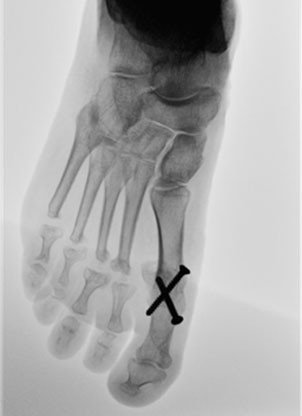

Bei schwerer Arthrose der Zehengrundgelenke mit Formveränderung der beteiligten knöchernen Strukturen und sehr kontrakten Fehlstellungen der Zehen ist es sinnvoll, die luxierten, praktisch funktionsuntüchtigen Gelenke zu entfernen. Die Hallux valgus – Deformität wurde unter Versteifung des Grosszehengrundgelenkes aufgerichtet, die 2. bis 5. Mittelfussköpfchen wurden entfernt, die Hammerzehen wurden unter Entfernung der prominenten Zwischengelenke stellungskorrigiert.

Dieser Eingriff konnte in Lokalanästhesie des Fusses durchgeführt werden, die Patientin blieb zwei Nächte im Spital. Die Nachbehandlung erfolgte in einem Barouk – Schuh für sechs Wochen, mit welchem eine Vollbelastung erlaubt war. Damit die Zehen 2 – 5 nach Entfernung der Mittelfussköpfchen nicht erneut ein Fehlstellung entwickeln, wurden sie währenddessen mit Kirschnerdrähten fixiert. Diese konnten anlässlich der ersten Röntgenkontrolle in der Sprechstunde entfernt werden. Die Erholungszeit nach diesem umfangreichen Eingriff benötigte mehrere Monate, da es über einen längeren Zeitraum zu Schwellungen des Fusses kommen kann.

Die Entfernung der Mittelfussköpfchen hat mehrere Vorteile: die dauerhaft entzündeten Gelenke sind nicht mehr vorhanden, ausserdem erreicht man eine Entspannung der äusserst kontrakten Weichteile, ohne welche die Rezentrierung der luxierten Zehen kaum gelingen würde. Metatarsalgien werden zuverlässig beeinflusst, Barfussgehen ist wieder möglich. Die Langzeitergebnisse dieser Operation sind sehr gut, die Patienten bei regelrechtem Verlauf zufrieden; zu signifikanten funktionellen Einbussen kommt es in der Regel nicht.